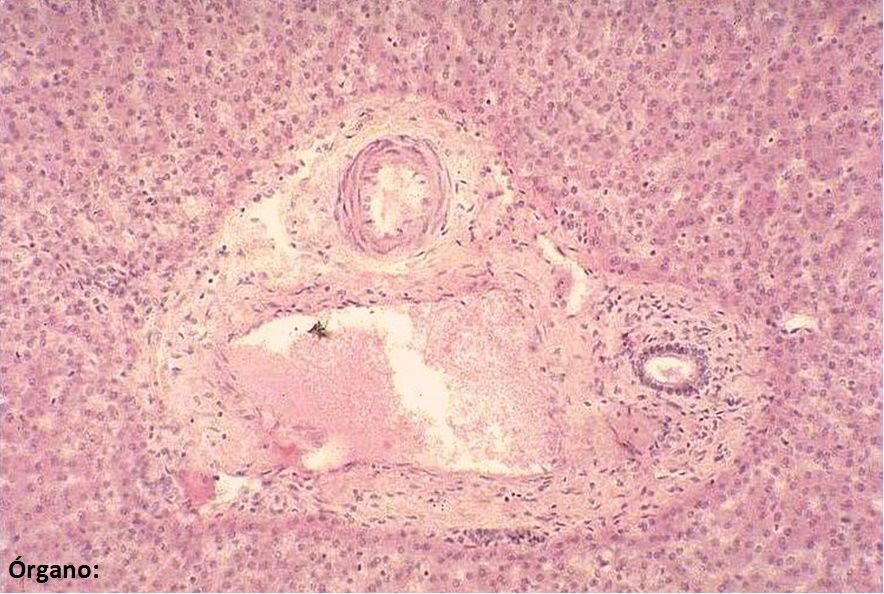

Escriba el nombre de las estructuras marcadas (dos palabras por cada estructura) y del órgano (abajo a la izquierda). Nota: tenga en cuenta los acentos y las faltas de ortografía.

Answer

• Conducto biliar

• Arteria hepática

• Vena porta

• Hígado